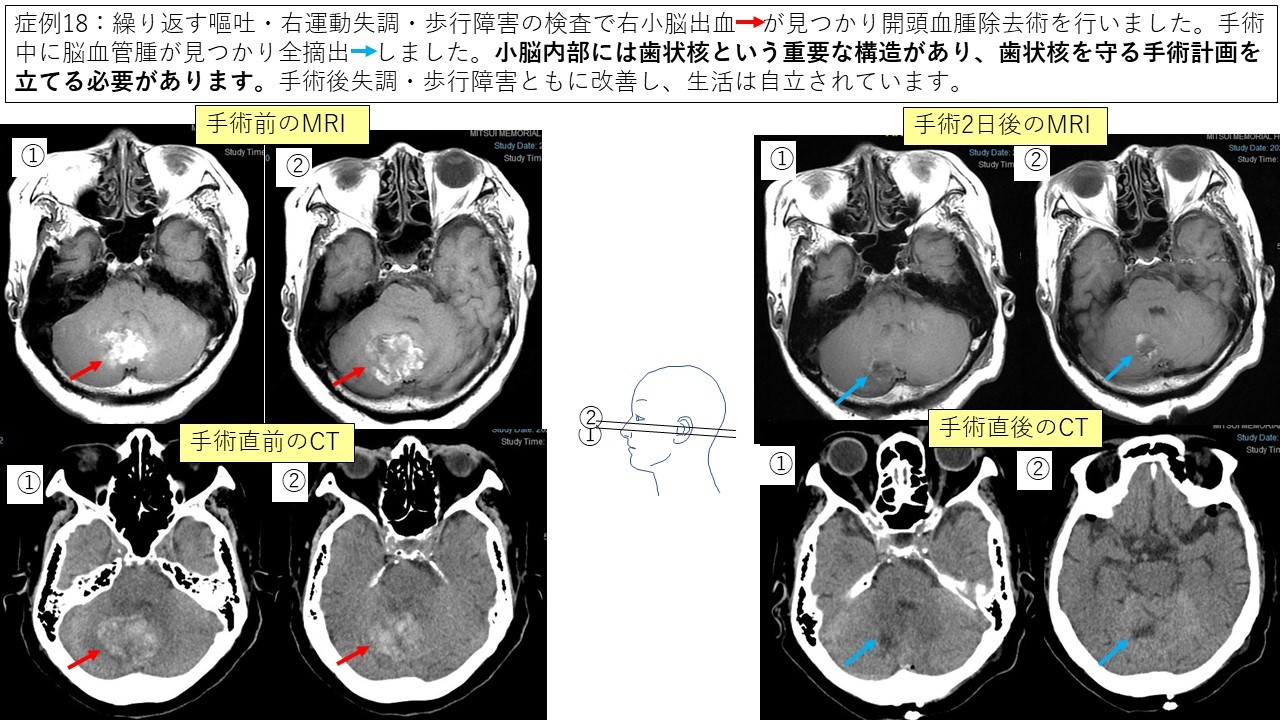

④血管腫 症例17 症例18

脳内血腫除去術

高齢者や全身合併症がある一部の脳内出血に関しては内視鏡による血腫除去術を行うことがあります。

手術時間は1時間から2時間で、患者さんへの侵襲が少ない手術ですが、出血の量が多くて脳のむくみがひどい場合は開頭術の方が有効です。